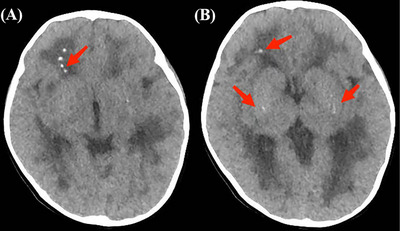

Results: A total of 15 patients was included, all presenting with various neurological symptoms, including developmental delay (100%), motor skill impairment (100%), language disability (78.6%), dystonia (93.3%), microcephaly (73.3%), sleep disorders (26.7%), regression (20.0%), vessel disease (6.7%), and epilepsy (6.7%). Neuroimaging revealed intracranial calcification (86.7%), cerebral atrophy (73.3%), and leukodystrophy (73.3%). Seven genes were identified, with TREX1 being the most common (40.0%, 6/15), followed by IFIH1 (20.0%, 3/15). Variant c.294dupA (p.C99Mfs*3) was detected in four unrelated patients, accounting for 66.7% (4/6) patients with the TREX1 variant. A literature review showed that TREX1 gene mutations in 35.6% (21/59) of AGS patients among the Chinese population.

Interpretation: Neurological symptoms are the most prevalent and severe presentation of AGS. Diagnosis may be considered when symptoms such as developmental delay, dystonia, microcephaly, brain calcification, and leukodystrophy emerge. TREX1 mutations are predominant in the Chinese population.